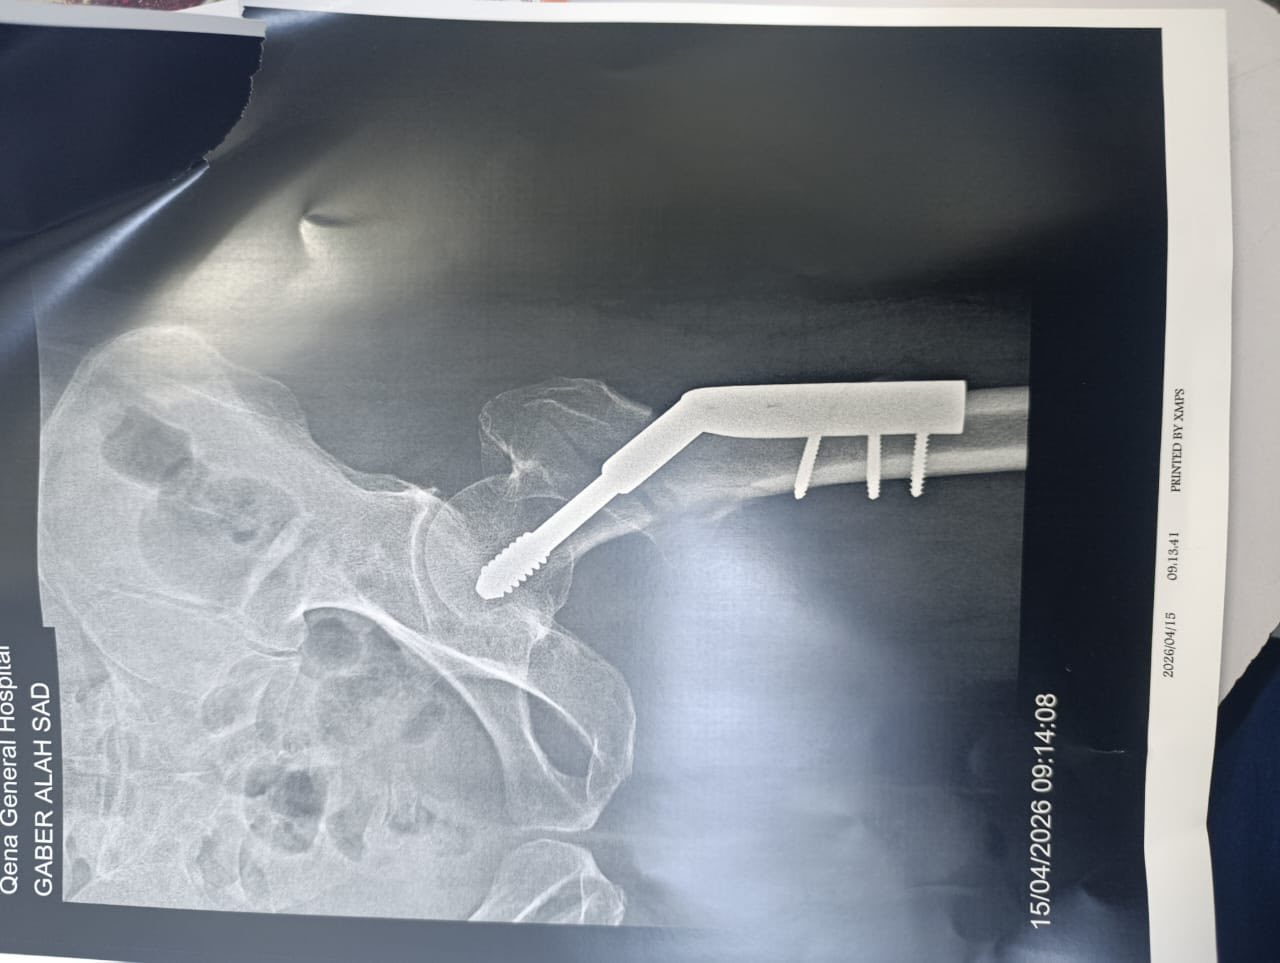

كما تم إجراء عملية تثبيت كسر بمدور عظمة الفخذ لرجل يبلغ من العمر 75 عامًا باستخدام الشرائح والمسامير، مع تحسن ملحوظ واستقرار الحالة.